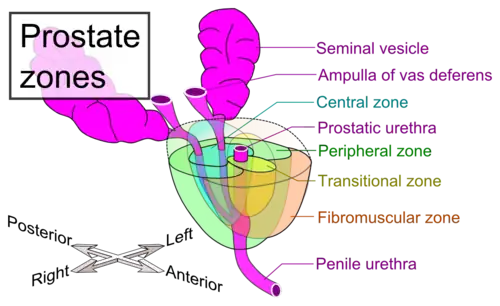

A estrutura interna da próstata foi descrita usando lóbulos e zonas.[4][1] Por causa da variação nas descrições e definições dos lóbulos, a classificação da zona é usada com maior predominância.[1] A próstata foi descrita como consistindo de três ou quatro zonas.[1][3] As zonas normalmente podem ser vistas em histologia, ou em imagiologia médica, como ultrassom ou IRM.[1][4] As zonas são:

| Nome | Fração da glândula adulta[1] | Descrição |

| Zona periférica (ZP) | 70% | Parte posterior da glândula que circunda a uretra distal e fica abaixo da cápsula. Cerca de 70–80% dos cânceres de próstata originam-se desta zona da glândula.[5][6] |

| Zona central (ZC) | 20% | Esta zona circunda os ductos ejaculatórios.[1] A zona central é responsável por cerca de 2,5% dos cânceres de próstata; esses cânceres tendem a ser mais agressivos e mais propensos a invadir as vesículas seminais.[7] |

| Zona de transição (ZT) | 5% | A zona de transição circunda a uretra proximal.[1] ~10–20% dos cânceres de próstata se originam nesta zona. É a região da próstata que cresce ao longo da vida e causa a doença de hiperplasia benigna da próstata.[5][6] |

| Zona fibromuscular anterior (ou estroma) | N/A | Esta área, nem sempre considerada uma zona,[3] é geralmente desprovido de componentes glandulares e composto apenas, como o nome sugere, de músculo e tecido fibroso.[1] |

Zonas da próstata

Zonas da próstata